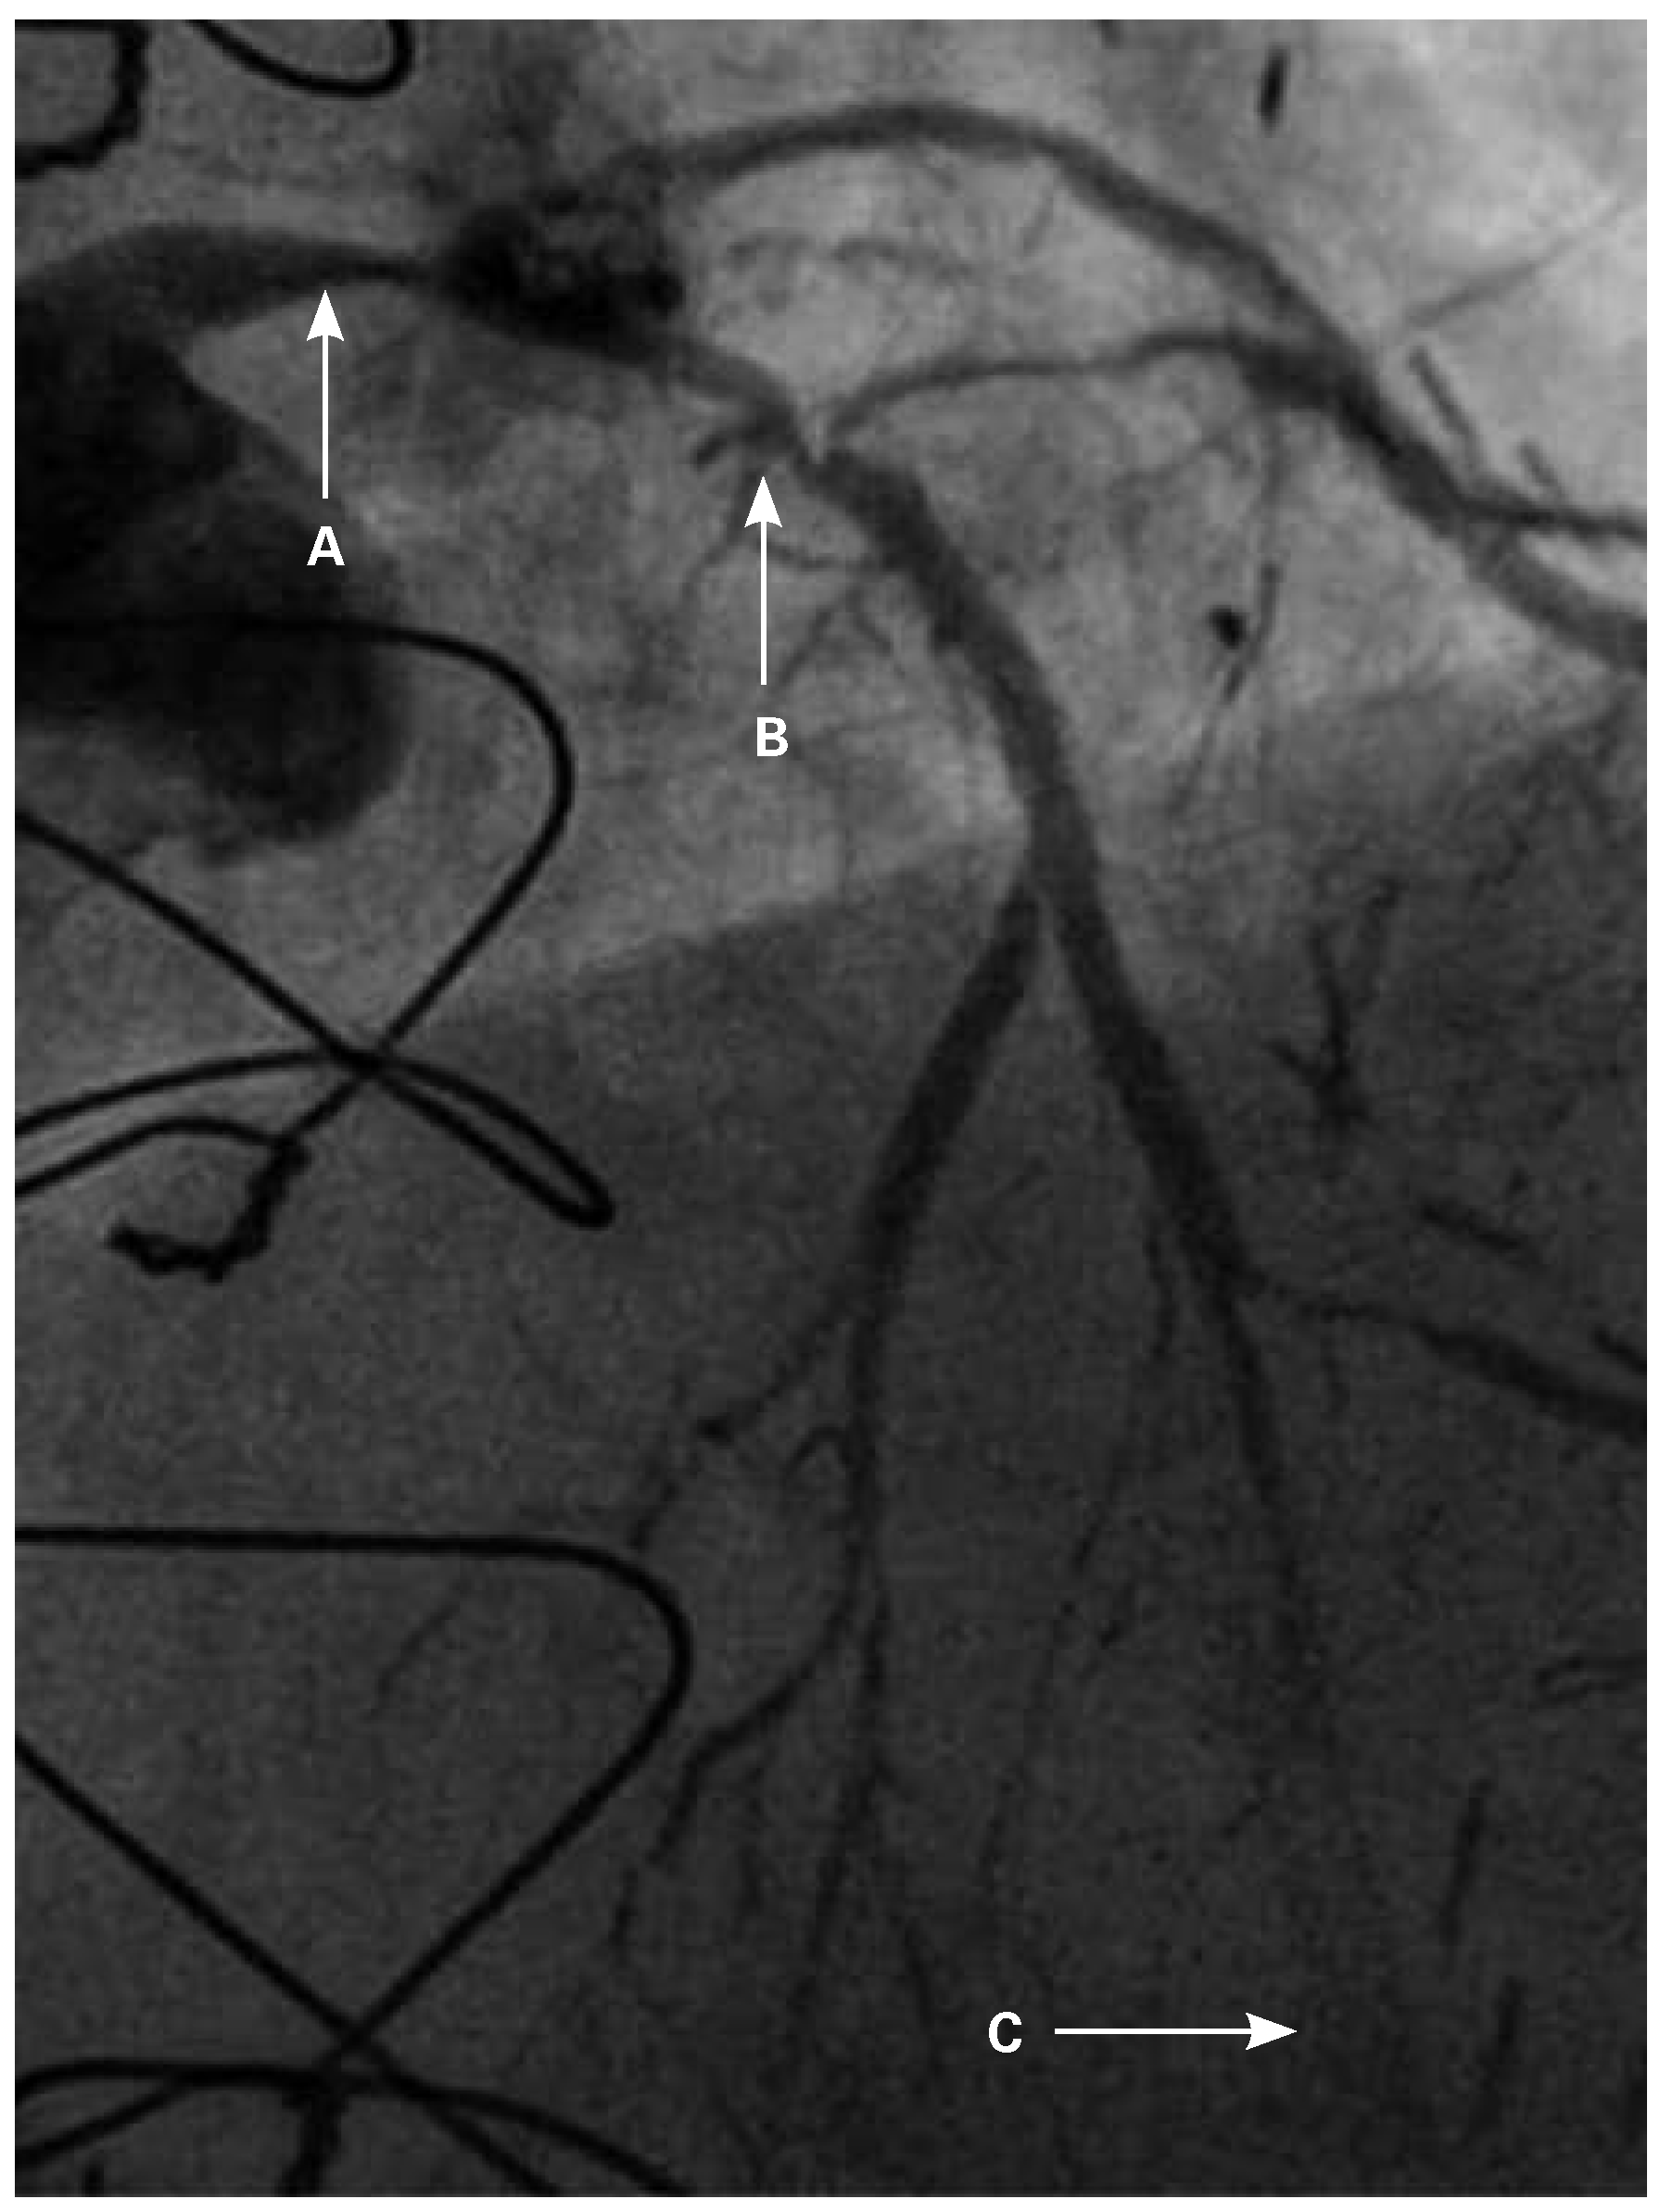

Following RA, both LAD and diagonal were wired with ease using separate Runthrough (Terumo, Japan) wires. Predilatation of both bifurcation limbs was undertaken using 1.5 × 15 mm Trek (Abbott) and 2.0 × 10 mm Sapphire (Orbus-Neich, Hong Kong, China) semicompliant balloons, which both expanded well at nominal pressure. Intending to perform an elective T-stent strategy, a 2.25 × 28 mm Promus Premier DES was deployed at 18 Atm in the diagonal branch, landing proximally at the ostium of this vessel (Figure 3). After removal of the diagonal wire, a 3 × 38 Promus Premier stent (Boston Scientific) was sited from the origin of the LMS across the first diagonal and deployed at 18 Atm (Figure 4). The diagonal branch was then rewired with the runthrough wire. A kissing inflation was performed at 12 Atm using a 3.5 × 12 Quantum (Boston Scientific) and 2.5 × 12 Sapphire noncompliant (NC) balloons in LAD and diagonal, respectively (Figure 5A). The proximal LAD and LMS were then optimised using the 3.5 Quantum NC (LAD) and a Hiryu (Terumo) 4 × 10 NC (LMS) balloons at 22 and 18 Atm, respectively (Figure 5B). The final angiographic result was excellent (Figure 6). Intravascular ultrasound of the LMS was not undertaken as angiographically the LMS stent already appeared completely expanded and oversized. We opted not to intervene in the ostial left Cx in order to best preserve the geometry of the LMS stent.

Figure 5. LAO 30°, cranial 30° view. (A) Kissing inflation with a 3.5 × 12 Quantum NC and 2.5 × 12 Sapphire NC balloons in LAD and diagonal, respectively; (B) Hiryu (Terumo) 4 × 10 NC deployed in the LMS.